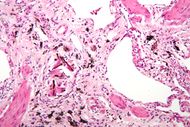

| Micrograph of asbestosis (with ferruginous bodies), a type of pneumoconiosis. H&E stain. | |

سحار رئوي أو تغبر الرئة pneumoconiosis هو اسم يطلق على مجموعة أذيات يسببها استنشاق جسيمات صلبة وتثبتها في الرئتين.

2ـ السحار بالأسبست (الأميانت) asbestosis: وهو تغبر الرئتين بغبار الأميانت وهي سيليكات معدنية ليفية تدخل في الصناعات العديدة، والتي تقدر بأكثر من ثلاثة آلاف مهنة في أوربا تستخدم ألياف الأسبست التي منها أنواع عديدة:

تحدث الأذية الرئوية نتيجة الاستنشاق المديد لغبار الأسبست (10 إلى 20سنة) وترتبط بشدة التعرض ولا تظهر الأعراض عادة إلا بعد التعرض المديد وخلال فترة طويلة من ترك العمل تتجاوز العشرين سنة أحياناً. ويشكو المصابون زلة تنفسية ويلاحظ تبقرط الأصابع clubbing (أي زيادة عرض السلامة الأخيرة وتحدب الأظافر نحو راحة اليد مما يعطي الأصابع شكل مضرب الطبل) وقد لوحظ أن الإصابة لا تقتصر على الأشخاص الذين هم باحتكاك مباشر مع غبار الأسبست فقد سجلت حالات عديدة لدى تعرضهم تعرضاً معتدلاً كعمال الدهان والكهرباء الذين يعملون جنباً إلى جنب مع عمال العزل في أحواض بناء السفن وحتى لدى زوجات العاملين في تحضير وتصنيع ألياف الاسبست واللواتي يغسلن ثياب أزواجهن، كما شوهدت حالات من الميزوتليوما الجنبية (أورام الوريقة المتوسطة) لدى القاطنين إلى جوار مصنع الأسبست في لندن والقاطنين بجوار مصنع تعدين الأسبست في جنوب أفريقيا.

إن الإصابة الرئوية التالية لاستنشاق الأسبست تشمل مايلي: حدوث التليف الرئوي الكتلي المترقي progressive massive fibrosis، وسرطان الرئة lung cancer، وورم المتوسطة الجنبية mesothelioma، وانصبابات الجنب pleural effusion، ولويحات الجنب الحميدة أو تليف الجنب pleural fibrosis.

أ ـ التليف الرئوي الكتلي المترقي P.M.F ويتظاهر بالبدء التدريجي مع ترقي زلة جهديه ونقص في تحمل الجهد إضافة لبعض الأعراض كالسعال والقشع عند غير المدخنين. ويعتمد التشخيص على وجود المظاهر الشعاعية من كثافات عقيدية وارتشاحات خطية غير منتظمة تظهر في الأقسام السفلية من الرئتين في البدء ثم تمتد للساحات الوسطى والعلوية مع تقدم الإصابة. ويتطور التليف الرئوي لدى 12 إلى 15% من الأشخاص المعرضين إذ يشاهد منظر الزجاج المغشى، ومع ترقي الإصابة يلاحظ منظر عش النحل بشكل ارتشاحات عقيدية مع ظلال فراغية هوائية، كما يكشف وجود تبقرط الأصابع في40% من الحالات. ويتطور القلب الرئوي في المراحل المتقدمة من التليف الرئوي كما تلاحظ الزرقة الشديدة.

يعتمد التشخيص على وجود قصة التعرض المهني المديد وإجراء التصوير الطبقي المحوري المليمتري ويتم تأكيد الإصابة بالخزعة الرئوية.